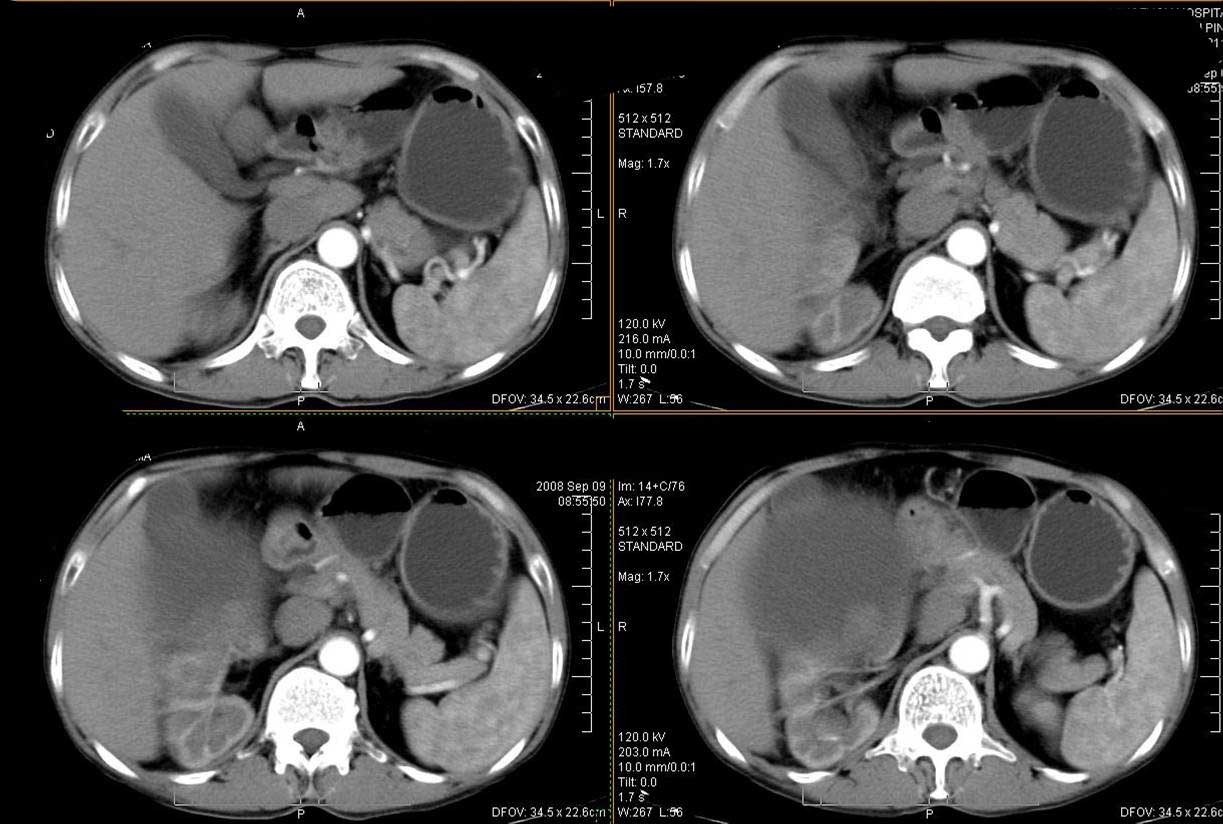

巨大囊性肿块,囊壁较厚有强化,有团片状钙化,病灶内下方灶内见片絮状高密度影,增强有轻中度强化,考虑囊性肾癌可能性大

右肾上部巨大的囊实性影,实性部分轻度强化。壁有钙化。考虑右肾囊腺癌。右肾盂积水。

定位;肾明显与病灶杯口相交,可以肯定病变来自右肾。

定性;病灶囊性为主,前下部含实性成分,及钙化,部分壁厚薄不均。

肾囊实性病变有;1,囊性肾癌2,囊性肾瘤。3,复杂囊肿。4,重复肾伴积水。然2、3壁相对规则。

综上考虑;囊性肾癌》重复肾伴积水。